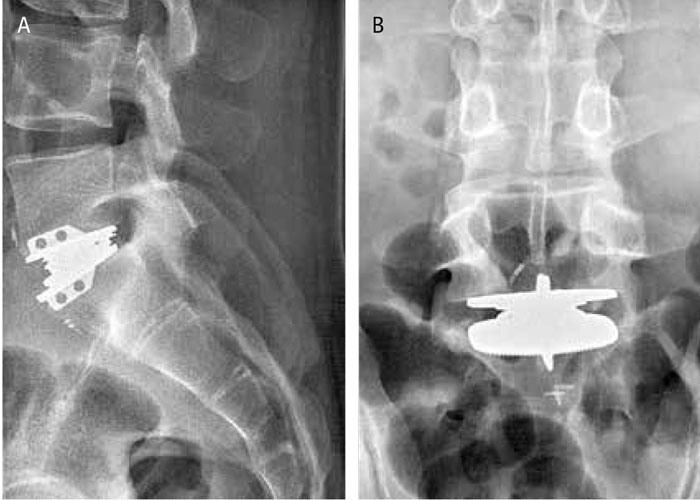

Medicinens ABC Orsaker, symtom och utredning

Medicinens ABC Behandling